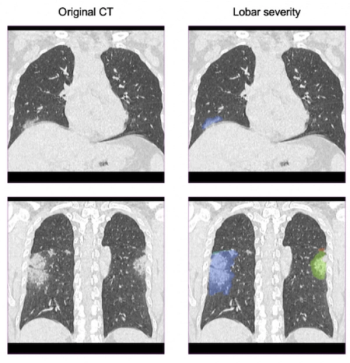

Reportedly offering improved delineation of pulmonary structures and greater accuracy with computed tomography (CT) values of pulmonary tissue, the artificial intelligence (AI)-powered LungQ 3.0.0. may facilitate enhanced precision and efficiency with interventional procedures such as lung volume reduction and ablation procedures.